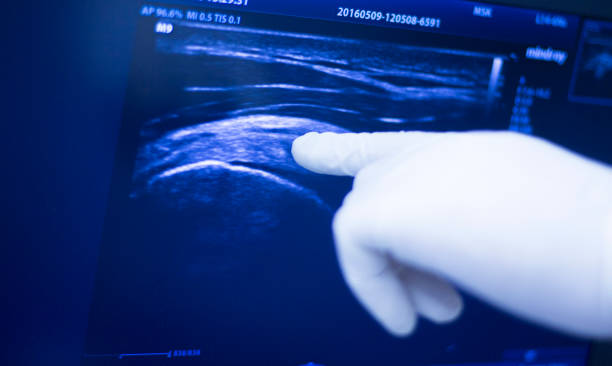

在促排卵治疗成功后,医生会在B超引导下,通过阴道超声引导穿刺技术取出成熟的卵子。